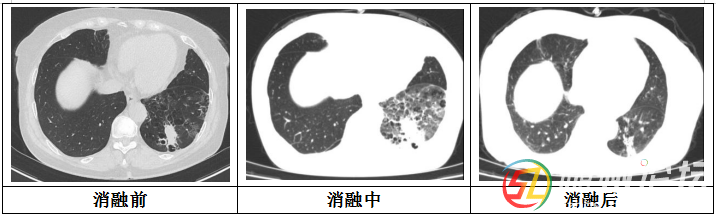

在MDT團(tuán)隊(duì)精密配合下,借助高分辨率CT的實(shí)時(shí)引導(dǎo),將一根細(xì)長(zhǎng)的冷凍探針精確穿刺布控到肺部目標(biāo)腫瘤內(nèi)部。啟動(dòng)冷凍系統(tǒng)后,清晰的“冰球”影像在屏幕上逐漸擴(kuò)大并完全覆蓋了腫瘤區(qū)域及其周圍的安全邊界。整個(gè)冷凍-復(fù)溫循環(huán)過(guò)程高效可控。手術(shù)耗時(shí)約1小時(shí),術(shù)后CT復(fù)查顯示患者肺部腫瘤細(xì)胞滅活效果極佳,第二天該患者便可下床活動(dòng)。